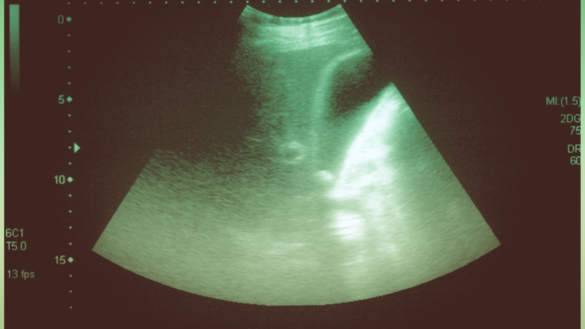

Prostatitt brukes som samlingsnavn for ulike plager i prostatakjertelen som er plassert i mannens kjønnsorgan. Prostatitt finnes i ulike former, én akutt og én kronisk. Den kroniske er er mest vanlig og innebærer at plagene har vedvart over lenger tid. Kroniske bekkensmerter er et annet navn på denne plagen. Hvorfor sykdommen oppstår, er ganske ukjent, men man antar at det beror på ulike typer bakterier. Den akutte formen kommer raskt, og beror ikke alltid på bakterier.

Sykdommen er et vanlig besvær, og de som har prostatitt blir ofte friske, iblant tar det likevel lang tid før man er kvitt symptomene. Prostatiss er en betennelse i prostatakjertelen som ligger rundt urinrøret akkurat der urinrøret forlater urinblæren og fortsetter ut i penis. Prostataens oppgave er å danne transportvæske for spermiene når de er på vei fra urinrøret til egget i livmorden. Når prostata blir betent, hovner kjertelen, blir øm og mykere i konsistensen. Betennelsen kan også påvirke omgivelsene i omkringliggende vev – som for eksempel musklene i bekkenbunnen.